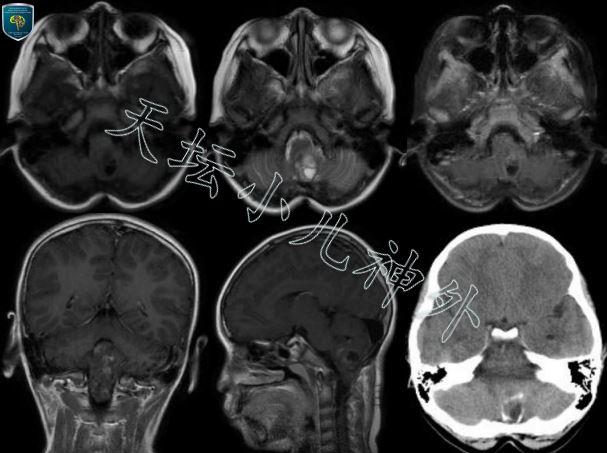

图1术前CT显示:枕部骨质缺损呈术后改变,后颅窝团块状密度影含钙化灶;MR提示:小脑及延髓背侧可见囊实性病变,长T1长T2,不均匀环状强化,考虑肿瘤复发。